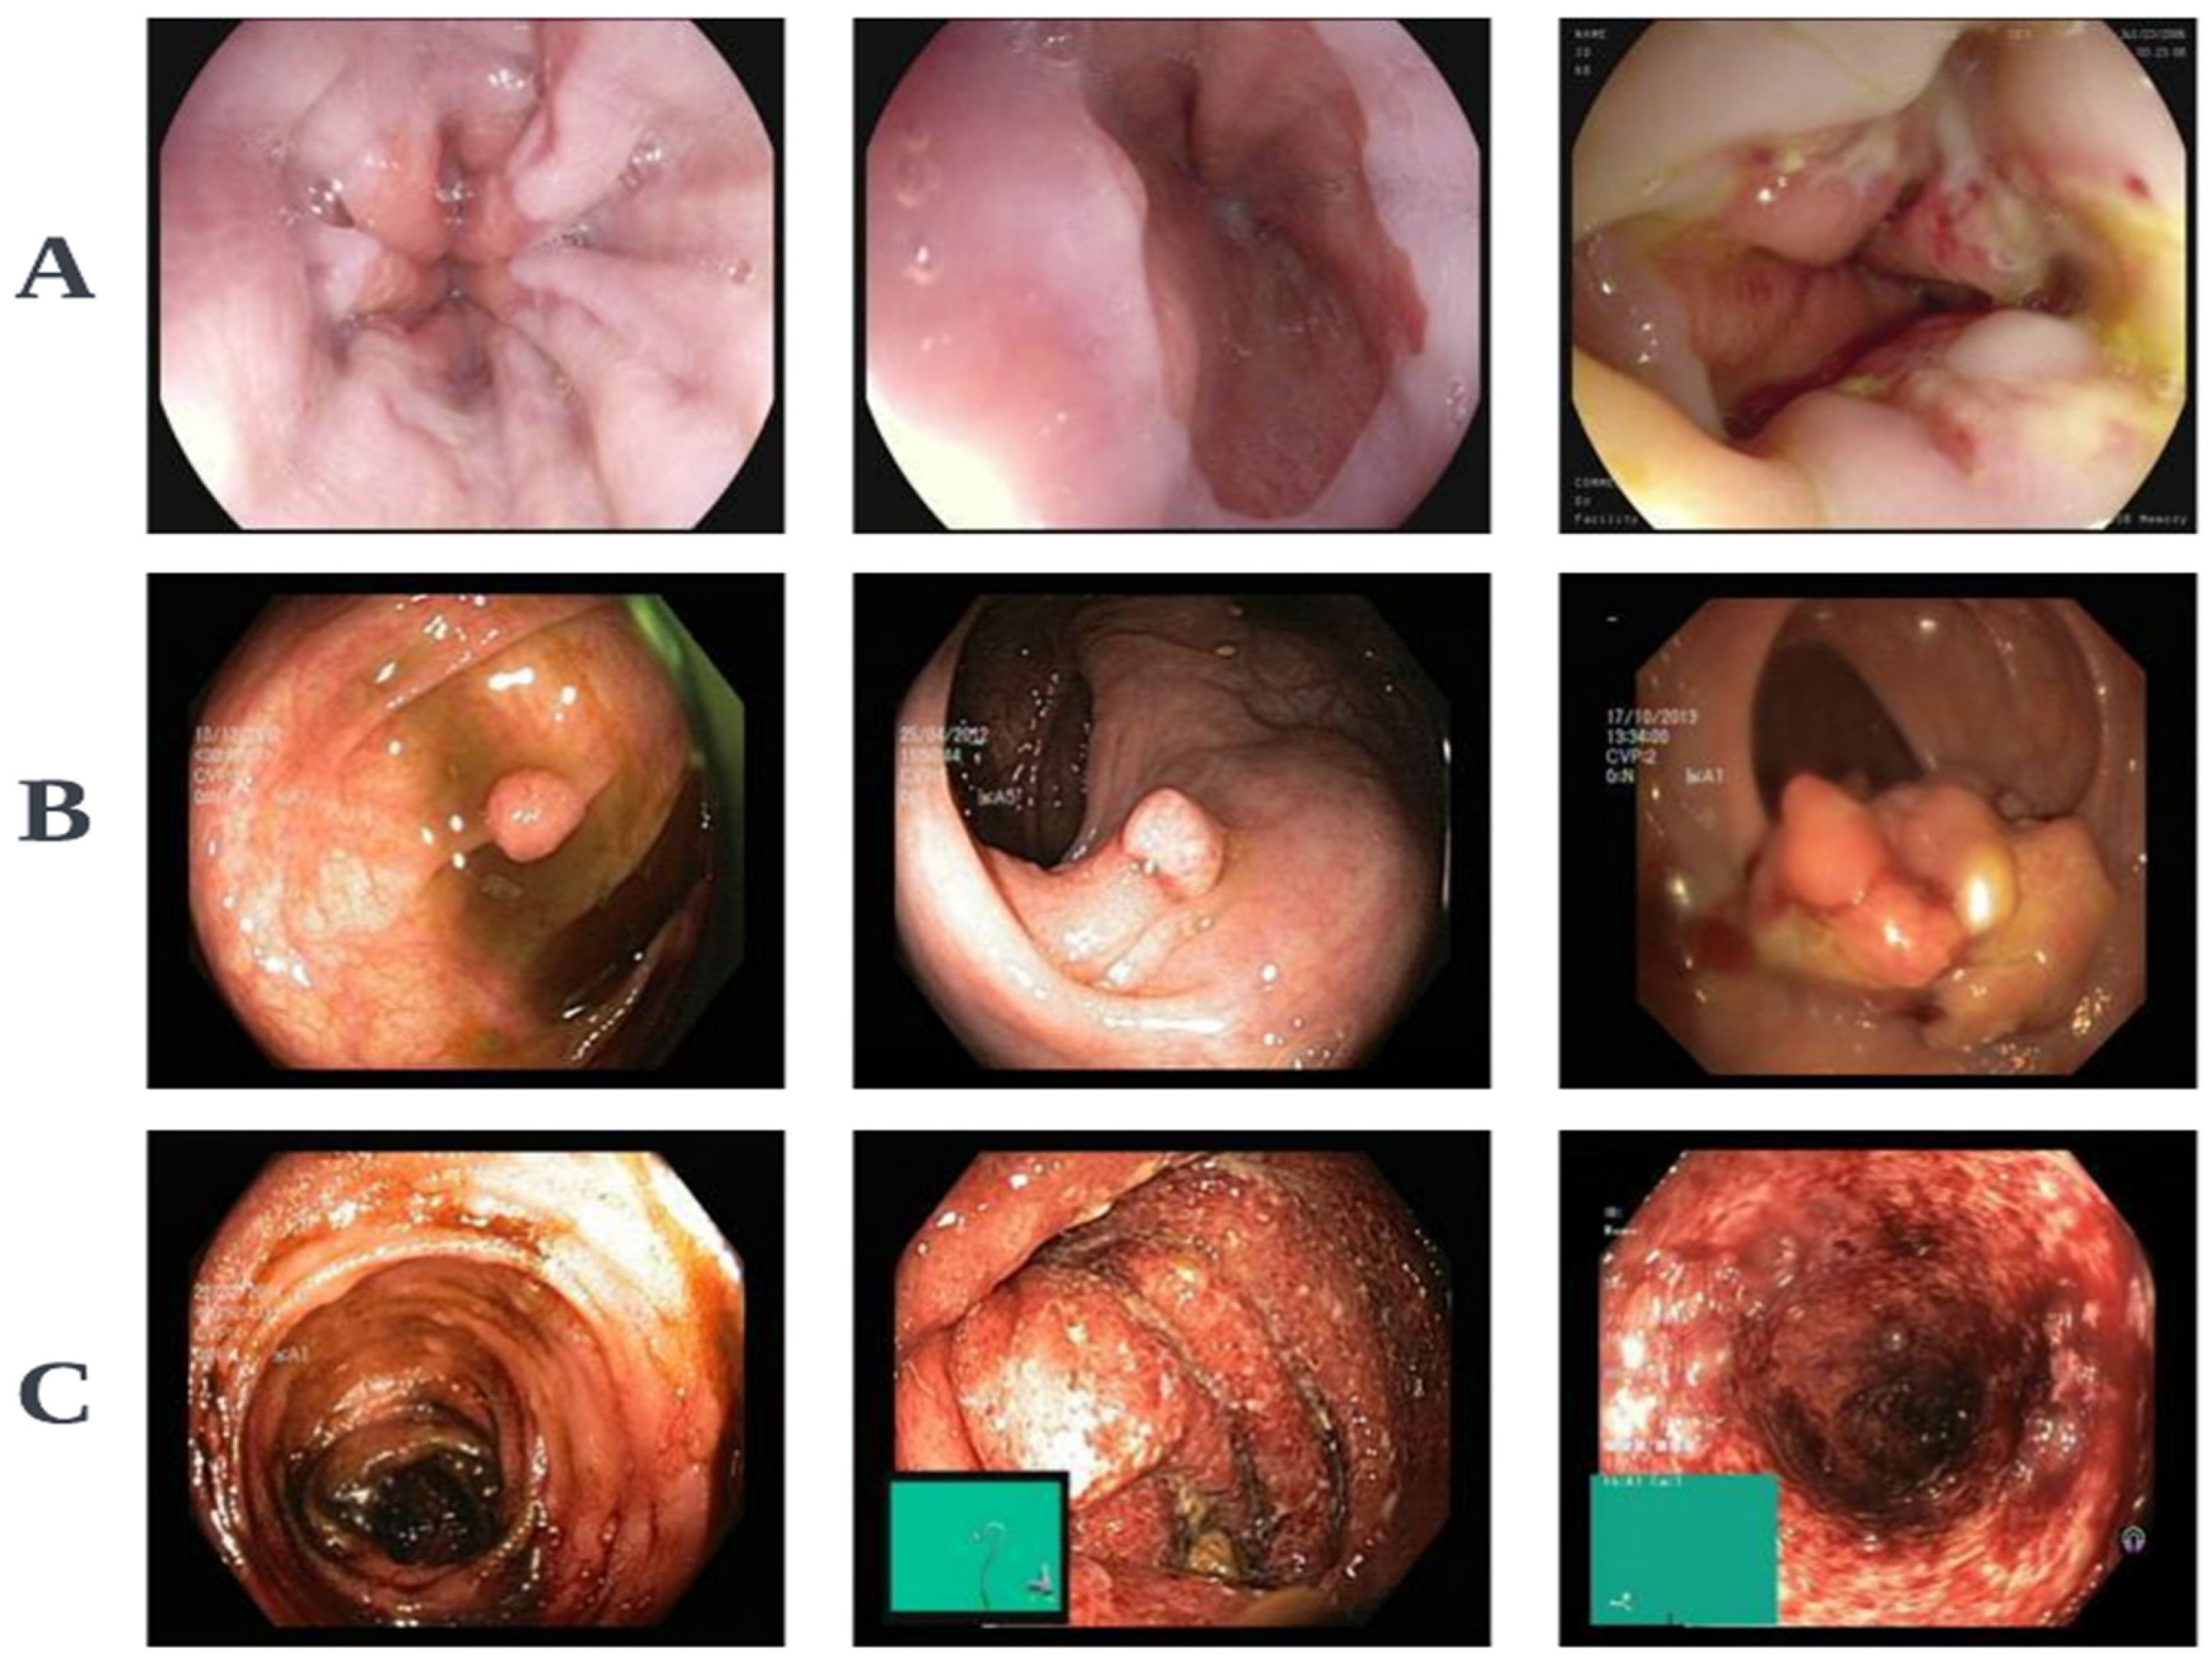

3.1. ViTCol: Vision Transformer-Based Classifier for CRC Detection

3.1.1. Motivation

3.2. PUTS: Vision Transformer-Based Polyp Segmentation

3.2.1. Motivation